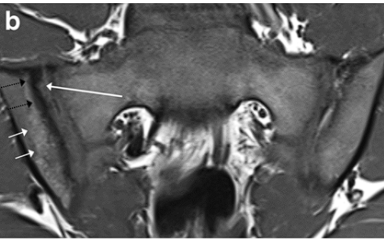

Lesões crônicas na RM na Spa? (4)

1. Esclerose;

2. Erosões;

3. Deposição de gordura;

4. Anquilose.

Esclerose (seta preta) e erosão (seta branca larga)